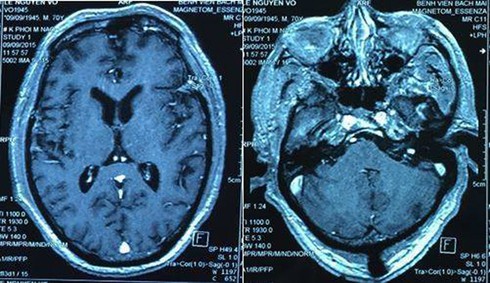

Hình ảnh chụp cộng hưởng từ sọ não cho thấy không còn tổn thương trong não. |